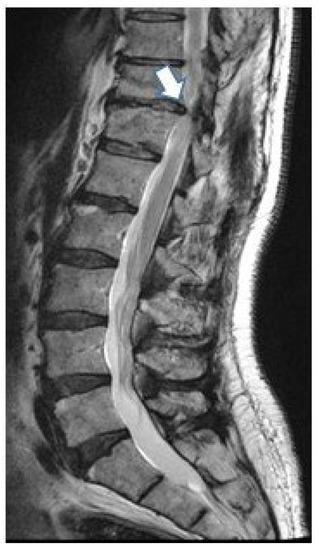

3.2. Case 2